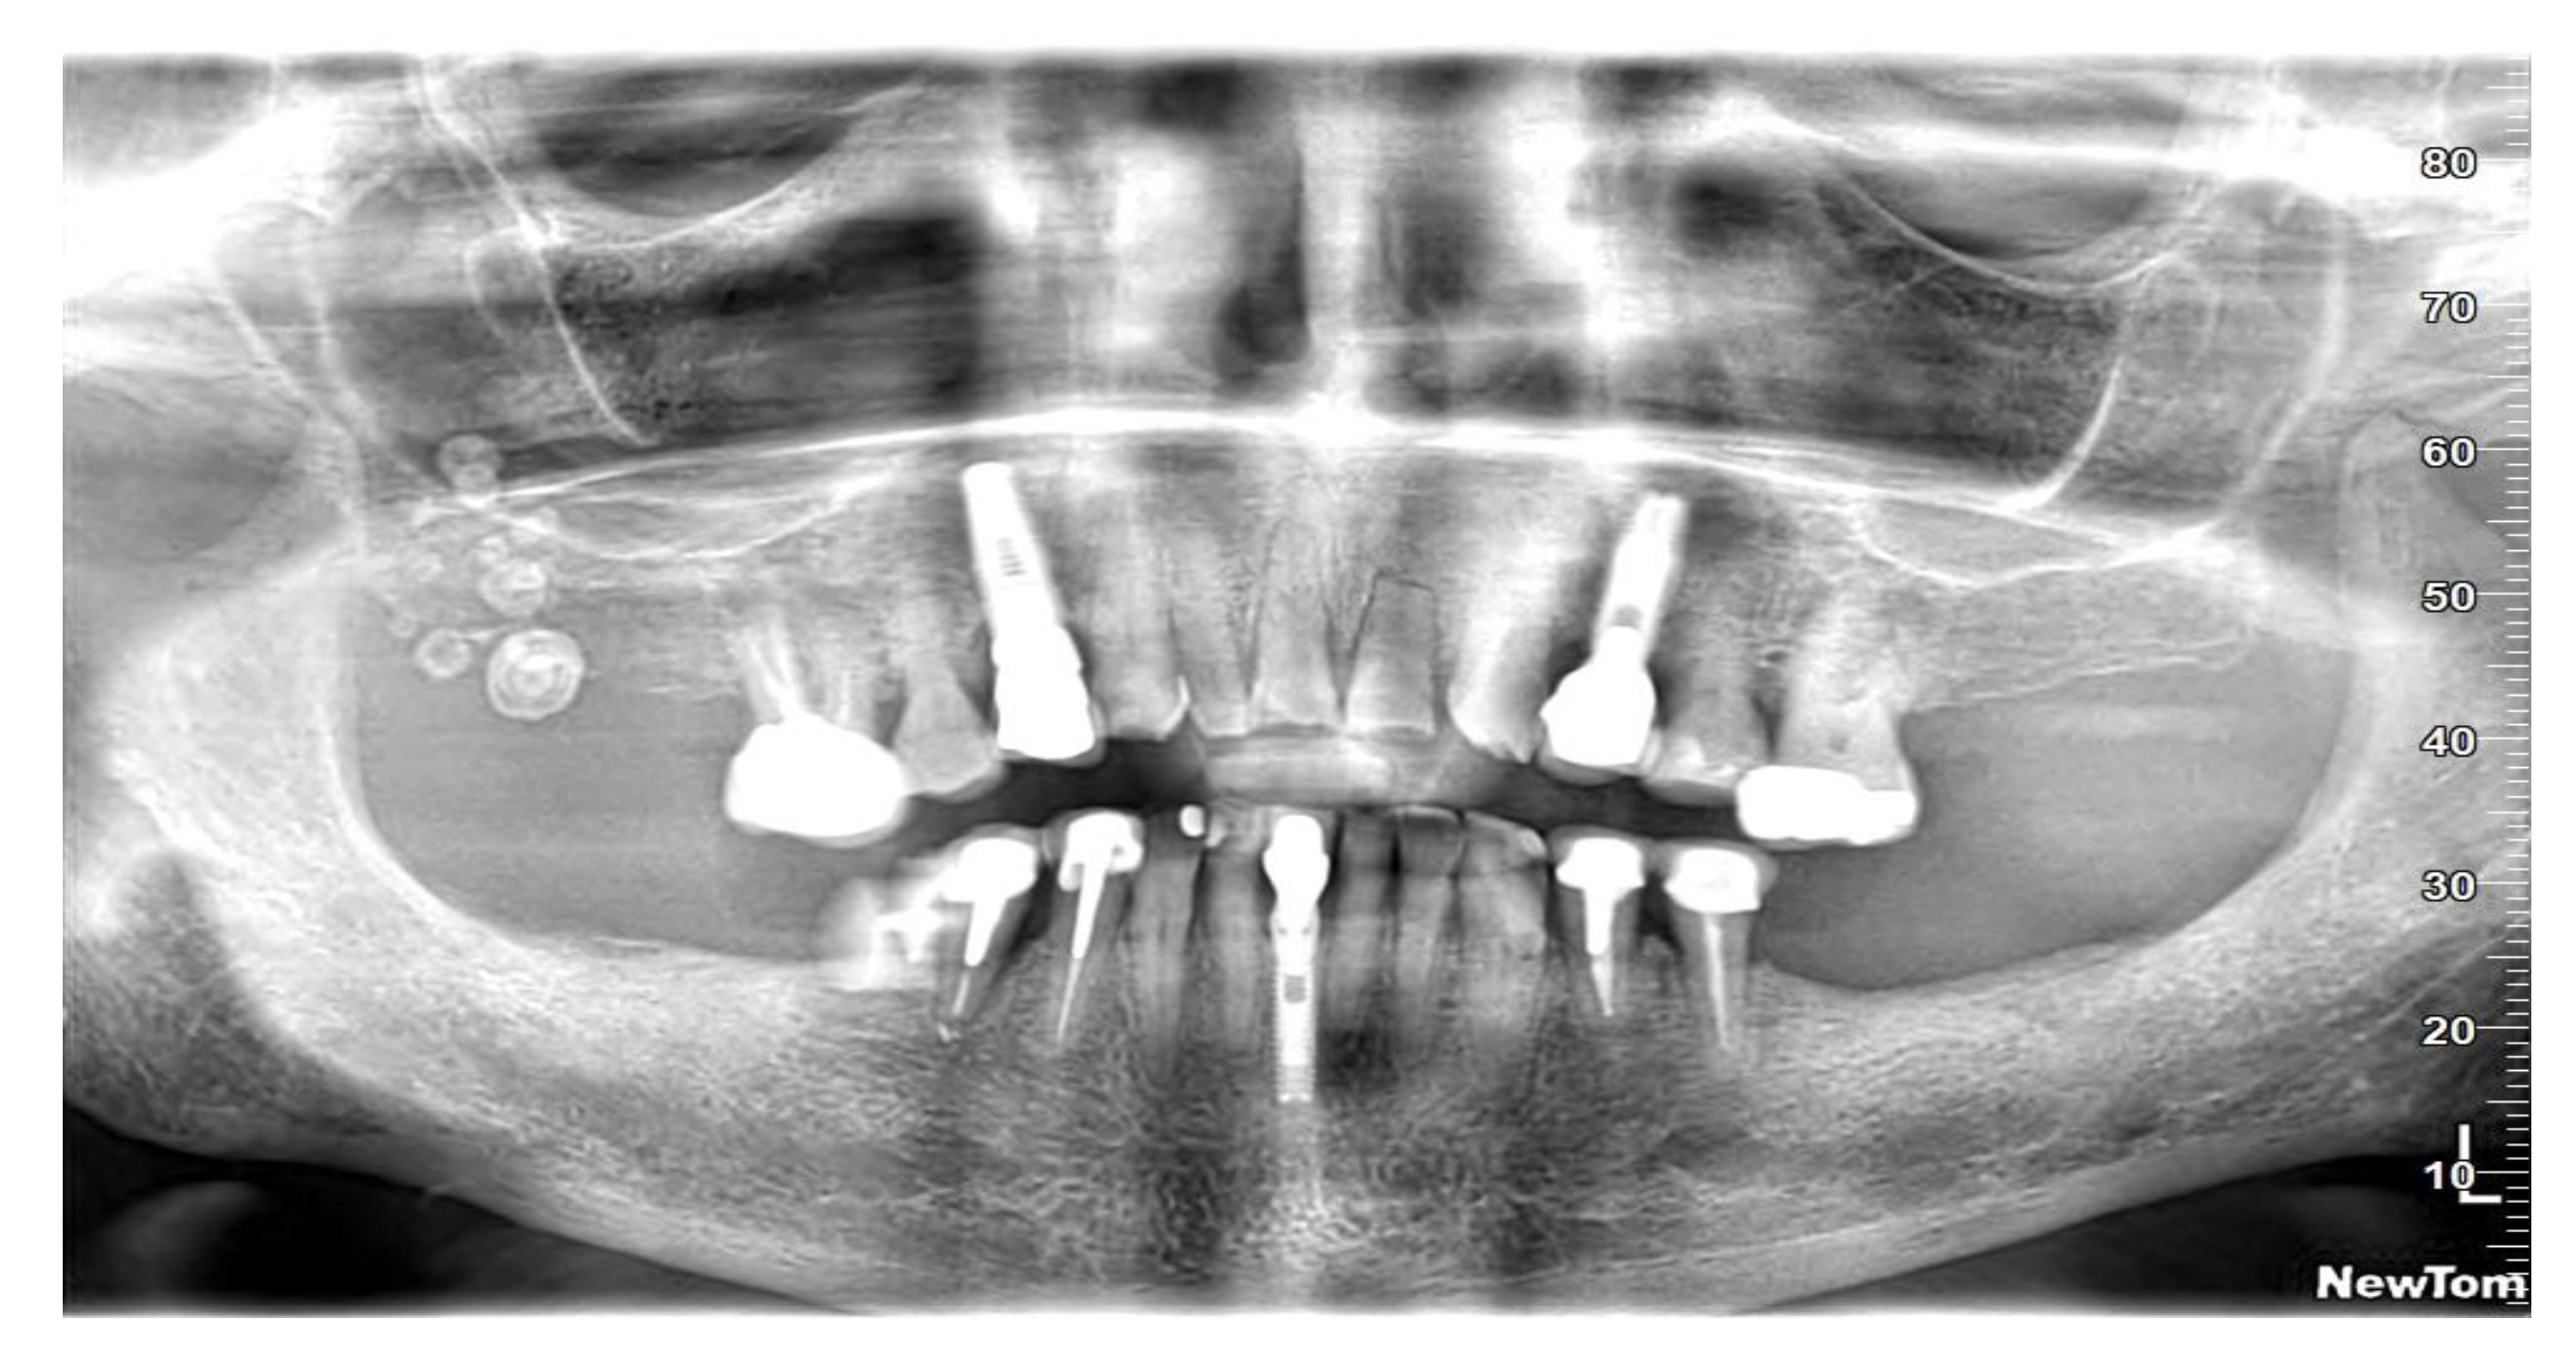

2. Case Presentation